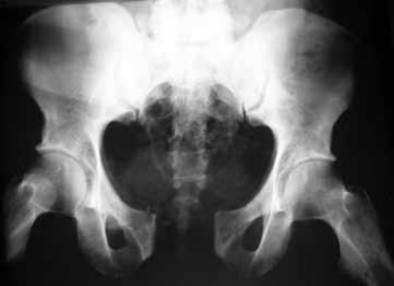

Figure 7Figure 7 is the pelvic radiograph of a 33-year-old man involved in a high-speed automobile crash. Examination reveals a blood pressure of 90/50 mm Hg and a pulse rate of 120/min. Radiographs of the chest and lateral cervical spine are normal. A CT scan of the abdomen does not reveal any intraabdominal bleeding. What is the most appropriate management for the pelvic fracture?